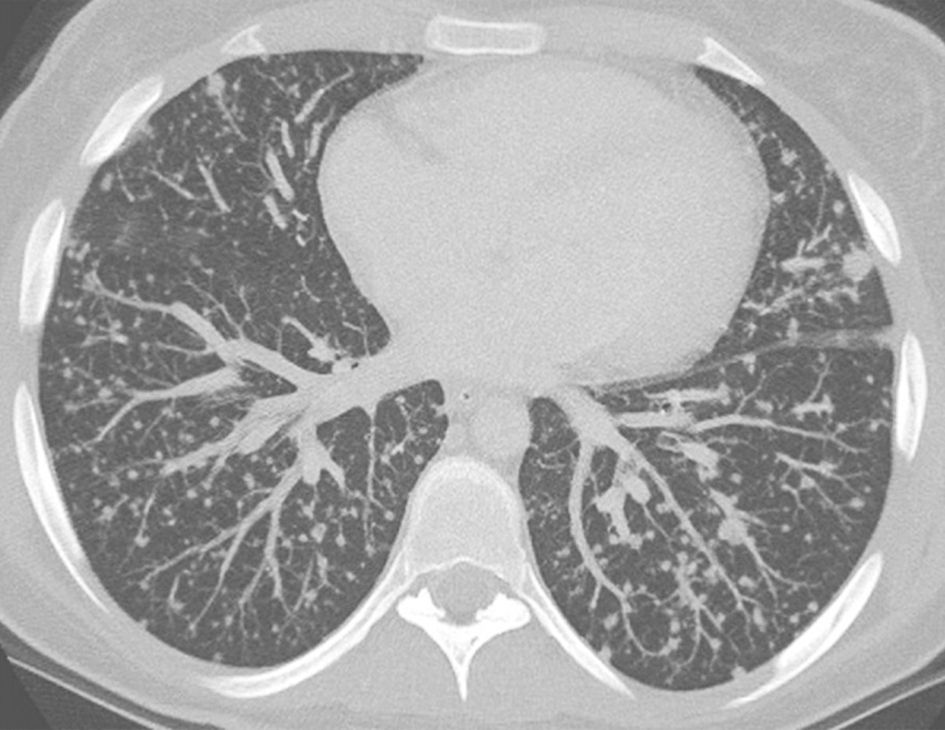

1小时条评论37岁男性患者,17个月前开始出现反复胸部隐痛,深吸气时明显,胸骨上段为主,无放射痛,与体位、运动无关,无发热、咳嗽、咳痰、咯血。肺部查体未见异常,后背散在皮疹。CT示两肺弥漫性粟粒样小结节影。抗结核治疗无效。本病例是感染性肺部疾病还是非感染性肺部疾病...